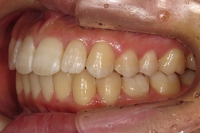

CASE4

前歯で物が噛み切れない。 顔が曲がって見える。

右のアゴが たまに痛い。

(19歳/女性)↓

概要・担当医コメント:

開咬/下顎の左右的偏位/顎関節症/非抜歯

動的治療期間28ヶ月(28回)/費用概算:65万円

顎関節症の改善を主目的として治療を開始しました.歯科矯正用アンカースクリューを使用することにより,上下とも非抜歯で治療出来ました.大臼歯の上下的位置を調整することで,顎関節に負担のかかり過ぎない噛み合わせにしました.